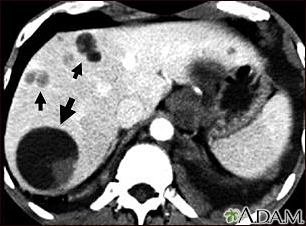

Liver echinococcus - CT scan